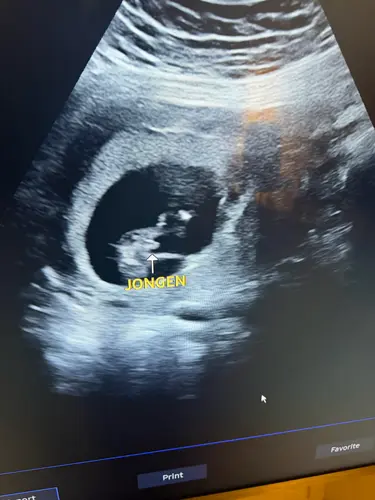

Dit was mijn potty shot bij de 13 weken echo en het is een meisje

Daar zie je toch duidelijk de 3 streepjes